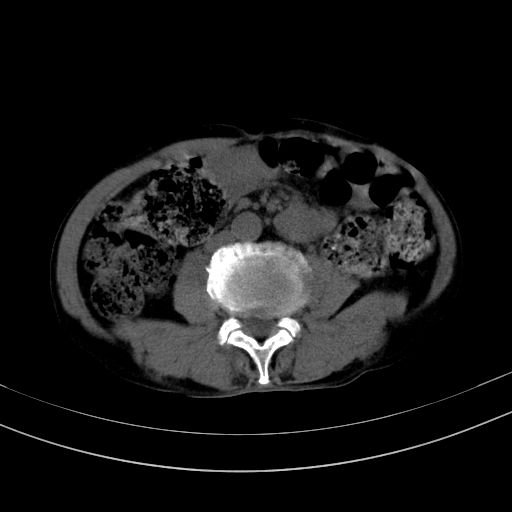

以下是引用37度在2010-1-9 14:37:00的发言:[br]1.双肾囊肿,左肾积水结石,.胆总管轻度扩张;[br]2.病灶在腹膜外,考虑纤维瘤。

以下是引用dyqct在2010-1-9 17:56:00的发言:[br]考虑:1.双肾囊肿,左肾积水结石、旋转不良。[br] 2.右侧腹直肌血肿或纤维瘤。[br]肠道准备不好。做个增强。